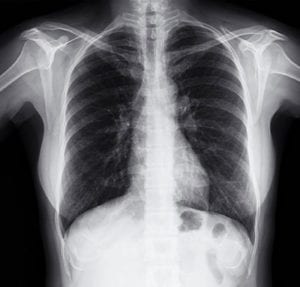

How Do Pulmonologists Diagnose Lung Diseases?

There are many lung diseases that impair the function of lungs. A patient with lung disease may experience chest tightness, shortness of breath, and difficulty breathing. These symptoms are what often bring patients to a doctor. Examples of lung diseases include asthma, pneumonia, emphysema, COPD, Read More

What is a Pulmonologist and What Do They Treat?

Pulmonology is a specialty of medicine that focuses on respiratory health. It aims to diagnose, treat, and prevent medical conditions that affect the lungs and respiratory tract. Pulmonologists undergo the same training as internists, but they are also specially trained to focus on pulmonology, Read More